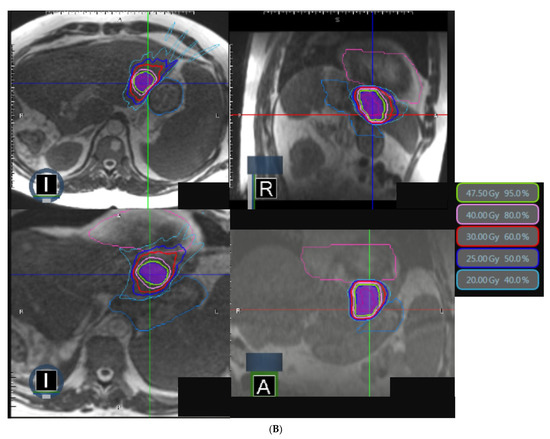

| PTV | |

| V95% (%) V100% (%) D95% (Gy) D1cc (Gy) | 95.9 (71.6–98.9) 50.0 (49.2–90.8) 47.5 (26.9–58.0) 52.0 (41.2–63.1)) |